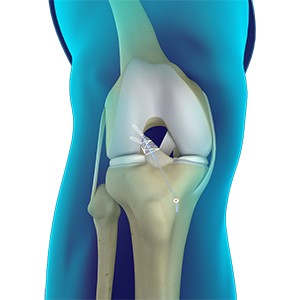

Primary ACL Repair

Traditionally, anterior cruciate ligament (ACL) tears of the knee are treated by reconstruction using a tendon or ligament autograft (tissue taken from your own body) or an allograft (tissue taken from a donor). Primary anterior cruciate ligament repair is a surgical procedure to repair the torn anterior cruciate ligament of the knee by placing sutures on the damaged anterior cruciate ligament and utilising a plastic anchor to reattach the anterior cruciate ligament back to the bone from where it ruptured away.